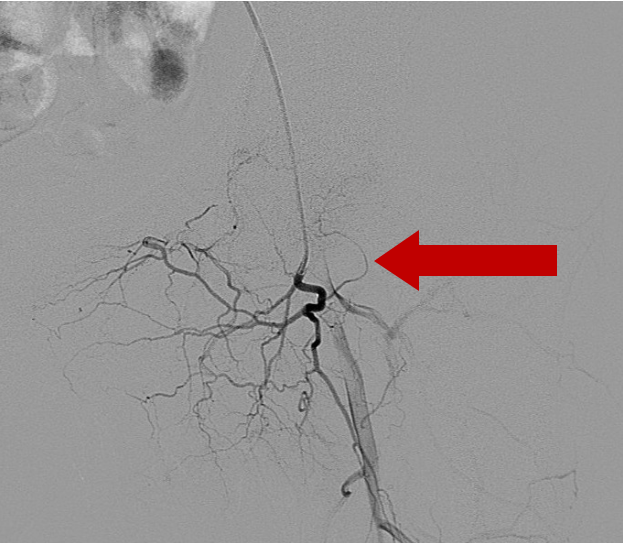

2020年8月7日介入手术,探查左股骨头供血动脉

介入手术中

经由皮肤穿刺技术,介入治疗得以开展,借助导管寻觅到股骨头供血动脉血管,以加压的形式灌注解痉、溶栓、活血化瘀等药物,达成改善股骨头血液循环的目标。缘于血液循环的改善,坏死的股骨头能够推动股骨头内坏死病灶的修复,有利于延缓或者避免病情的进一步发展,在延缓或避免病情进展方面具备积极作用。介入治疗主要适用于处于1期的患者 ,适用于处于2期的患者 ,也适用于处于3期的患者 。